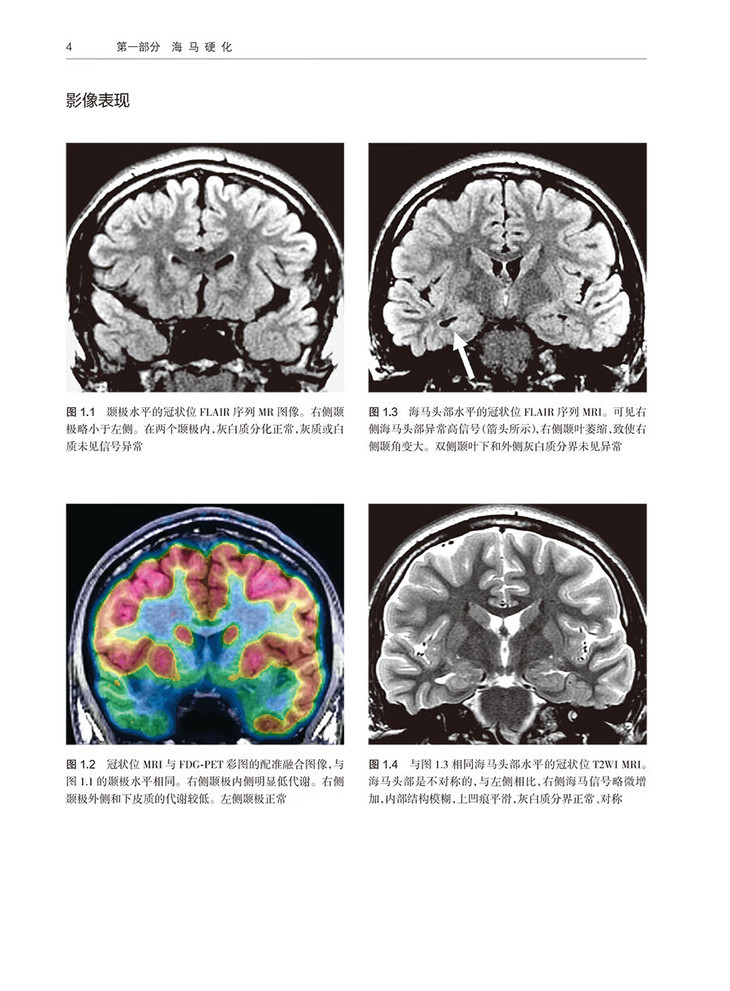

1 轻度单侧海马硬化 /3